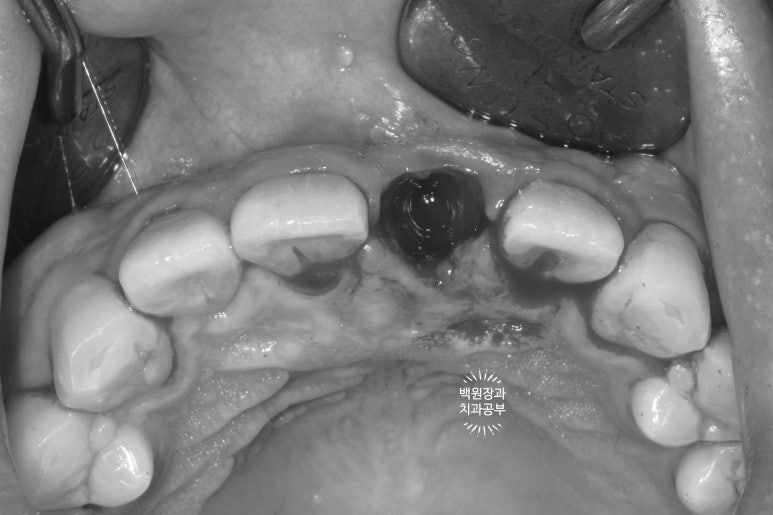

입천장 쪽에서 바라보았을 때, 이미 잇몸라인보다 깊은곳까지 부러져 있는 뿌리만 남은 치아를 보실 수 있어요.

예전에 신경치료를 해놓은 치아라 앞니 뿌리가 이미 검게 변해버린 상태입니다.